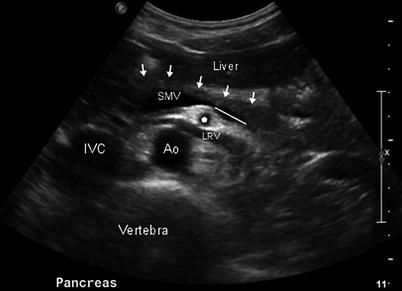

Run lateral off IVC courses anterior the Aorta

left renal vein - nut cracker can get pinched under SMA

runs off of the aorta laterally and posterior to the IVC

Right renal artery

It’s also longer than the left